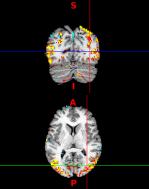

EEG (electroencephalography) is one of the most accessible techniques used to measure brain activity in humans. However, EEG measurements are affected by surrounding tissue and the spatiotemporal organization of the underlying neural activity that comprises the EEG signal is still hotly debated. Less debated is the neural activity that comprises the intracortical LFP (local field potential) measure. Our focus is to reconcile the spatiotemporal relationship between LFPs and EEG to better understand what neural activity supports EEG signals, using novel cross-species data and statistical analysis.

We also develop unsupervised statistical learning methods for medical signal and image processing, and tools for data visualization and dimension reduction. Applications include artifact removal in electrophysiology data, feature extraction in microarray data, and identifying brain networks in functional magnetic resonance imaging (fMRI).